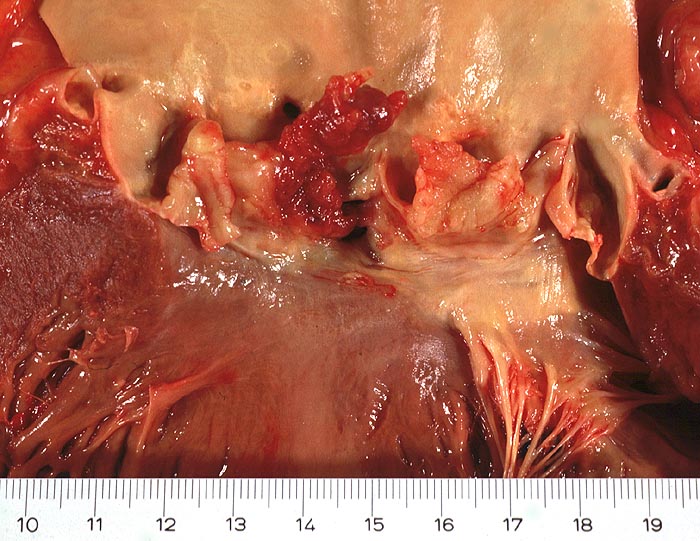

Ulzeropolypöse infektiöse Endokarditis

Aortenklappe

Ulzera mit partieller Zerstörung der Taschenklappen und polypöse Vegetationen.

Nachweis von Staphylokokkus epidermidis im Blut und im Milzabstrich. Zahlreiche septische Embolien im mehreren Organen. Trikuspidalklappenendokarditis.

Der Patient wurde von der Polizei komatös in der Wohnung aufgefunden und starb 20 Minuten nach Spitaleinweisung.